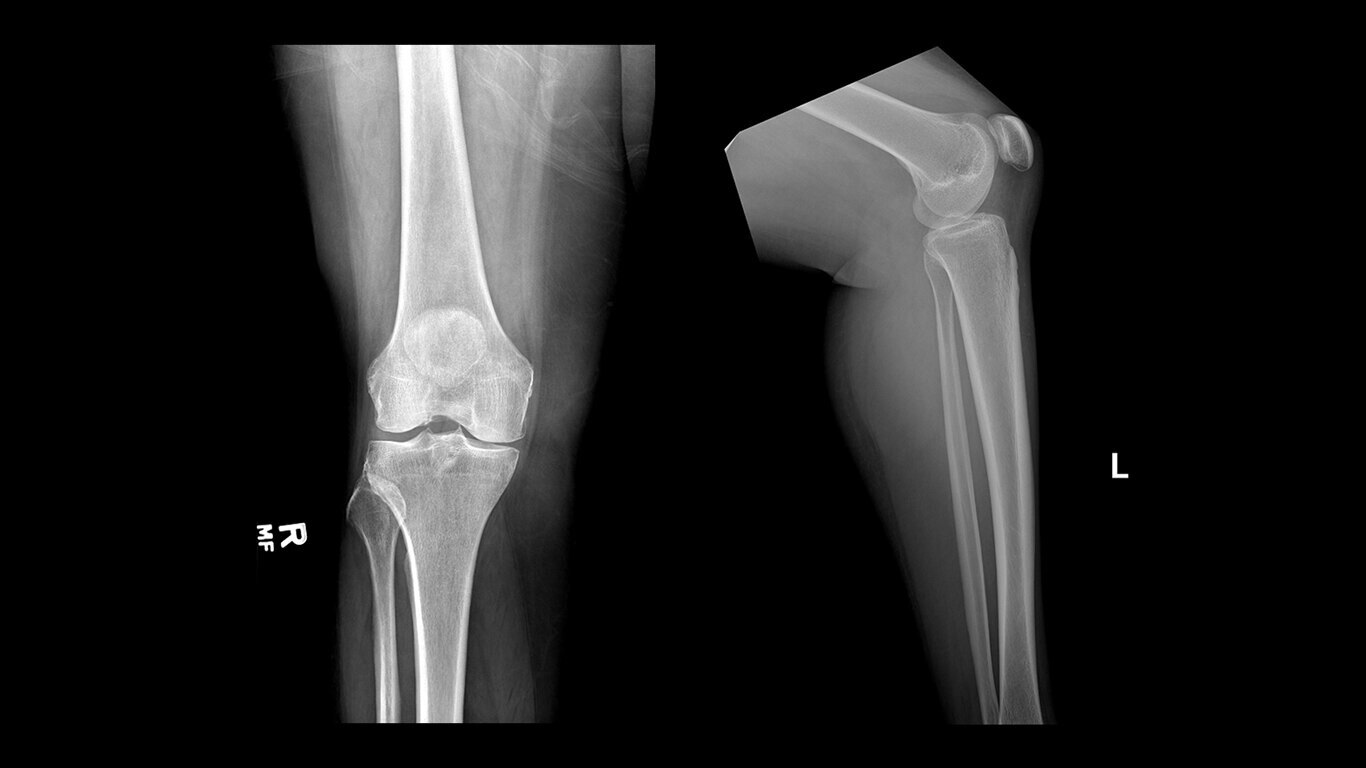

Uncompromised image quality

Capture high-resolution images with powerful, glassless detectors that weigh 40% less than previous generations3